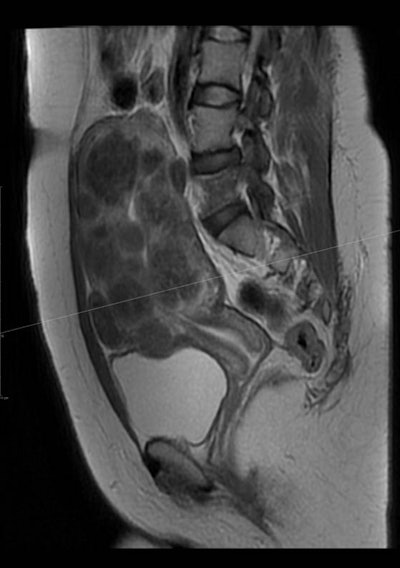

خلال عملية معالجة الورم الليفي الرحمي بالقثطرة.

تتميز معالجة الأورام الليفية الرحمية عن طريق القثطرة بأنها أبسط و بأن نسبة المشاكل والاختلاطات أقل مقارنة بالاستئصال الجراحي حيث يتم اجراء القسطرة بدون تخدير عام و ياخذ الاجراء 45 دقيقة و تخرج المريضة من المشفى في نفس اليوم.

تبعاً لما يعتقد بأنها اكبر دراسة الأولى في الشرق الأوسط فإن معالجة الأورام الليفية عن طريق القثطرة تتم عبر قطع التروية الدموية للأورام الليفية المسببة للاعراض وتتمتع بنسب متقاربة مع الجراحة من ناحية الأنجاب للنساء اللواتي يرغبن بالحمل.